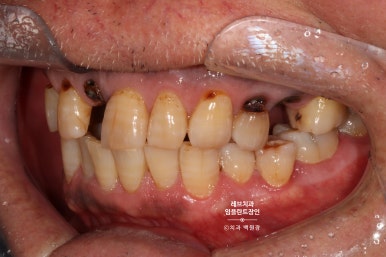

보시면 가만히 있어도 치아와 잇몸 사이에서 고름이 올라오는 것을 보실 수 있어요..

흡연을 좋아하시던 분이었고, 만성 치주염이 심해져서 치주농양까지 진행된 상태입니다.

치과용 파노라마 사진에서도 왼쪽 위 송곳니 주변으로 잇몸뼈가 사라진 것을 보실 수 있는데요,

확대해볼 수 있는 치근단 방사선 사진을 보시면, 송곳니 뿌리 주변으로 거무딩딩하게 뼈가 없어진 것을 보실 수 있습니다.

만성치주염으로 상당히 많은 양의 잇몸뼈가 파괴되었죠.